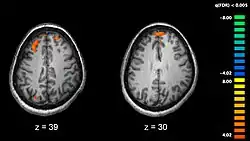

The areas most actively involved in episodic encoding and retrieval are the medial temporal lobe (hippocampus) and the prefrontal lobe.

Recent research using neuro-imaging technology including PET and fMRI scanning has shown that there is an extensive amount of distributed brain activation during the process of episodic encoding and retrieval. Among the various regions, the two most active areas during the constructive processes are the medial temporal lobe (including the hippocampus) and the prefrontal cortex.[15] The Medial Temporal lobe is especially vital for encoding novel events in episodic networks, with the Hippocampus acting as one of the central locations that acts to both combine and later separate the various features of an event.[16][17] Most popular research holds that the Hippocampus becomes less important in long term memory functioning after more extensive consolidation of the distinct features present at the time of episode encoding has occurred. In this way long term episodic functioning moves away from the CA3 region of the Hippocampal formation into the neocortex, effectively freeing up the CA3 area for more initial processing.[17] Studies have also consistently linked the activity of the Prefrontal Cortex, especially that which occurs in the right hemisphere, to the process of retrieval.[18] The Prefrontal cortex appears to be utilized for executive functioning primarily for directing the focus of attention during retrieval processing, as well as for setting the appropriate criterion required to find the desired target memory.[15]